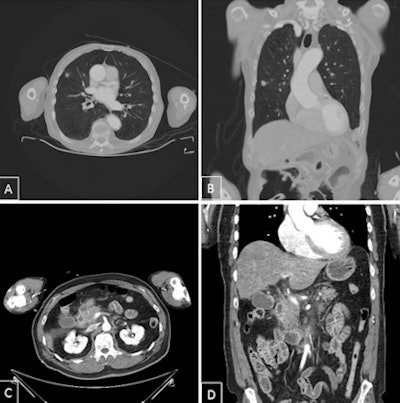

Secondary findings of category 1. A and B: Polytrauma CT with coronal multiplanar reconstruction; lung lesion on the right is suspicious for malignancy. Suspicious for peripheral bronchial cancer. C and D: Polytrauma CT with coronal multiplanar reconstruction. Acute exudative pancreatitis.In another 13.3% of patients with secondary findings, speedy diagnostics and treatment seemed advisable. Other findings involved either harmless normal variants or findings that did not require urgent attention.